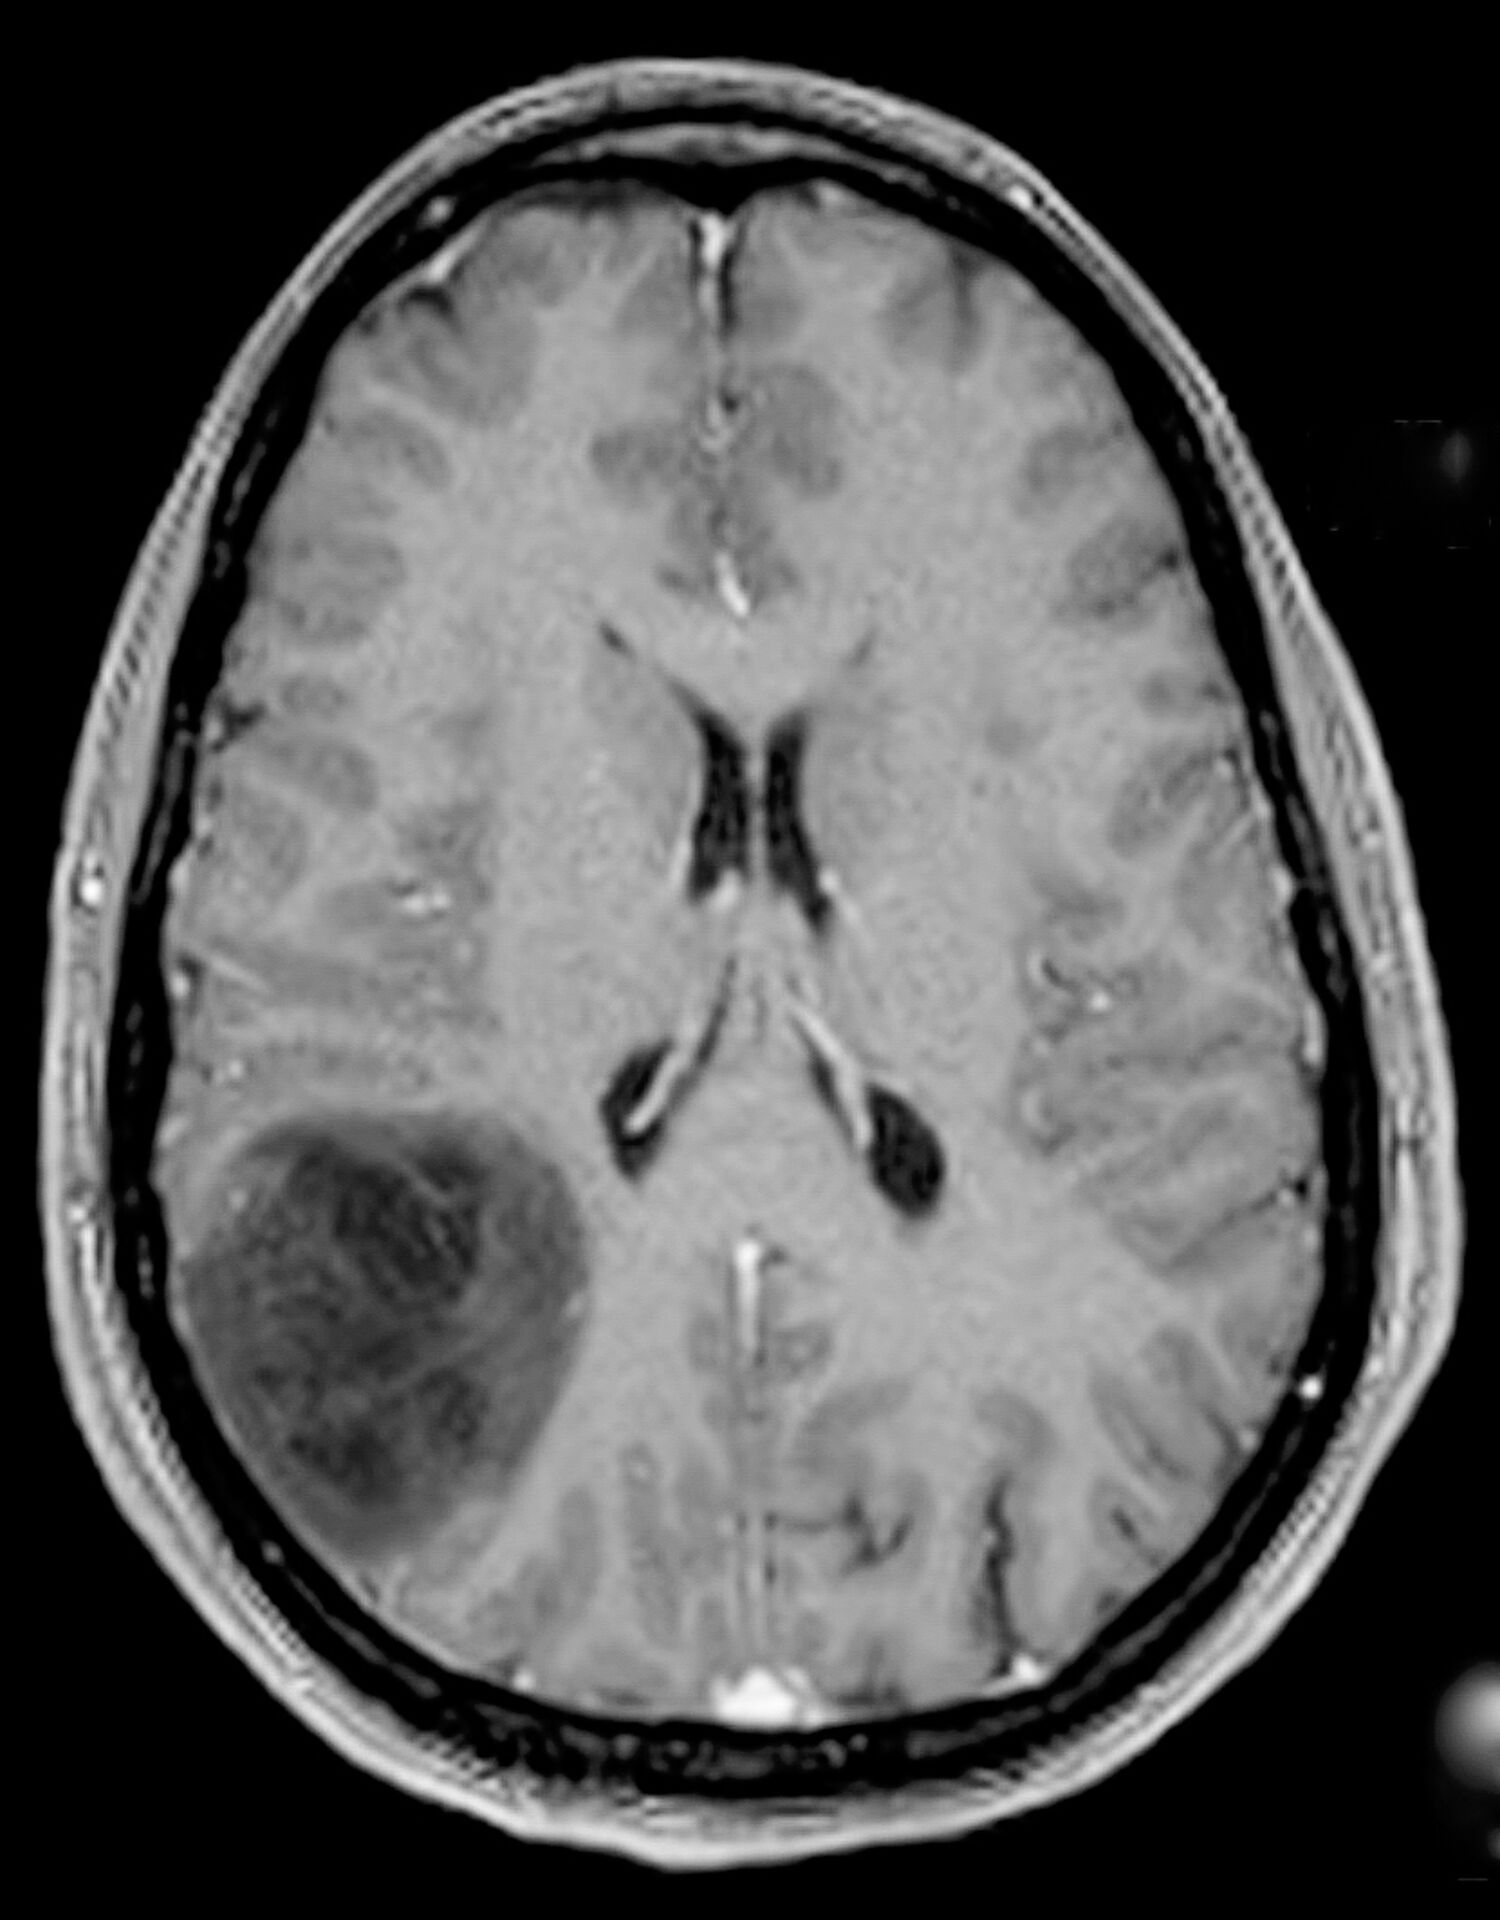

Le diagnostic repose sur l’IRM cérébrale, qui permet de visualiser la tumeur, d’évaluer son extension et ses rapports avec les structures cérébrales avoisinantes. Le diagnostic de certitude est établi par l’analyse histologique et moléculaire du tissu tumoral prélevé lors de la chirurgie. Ces informations précisent le sous-type de gliome et orientent la stratégie thérapeutique. Chaque dossier est discuté en réunion de concertation pluridisciplinaire regroupant neurochirurgiens, oncologues, radiothérapeutes et neuroradiologues.